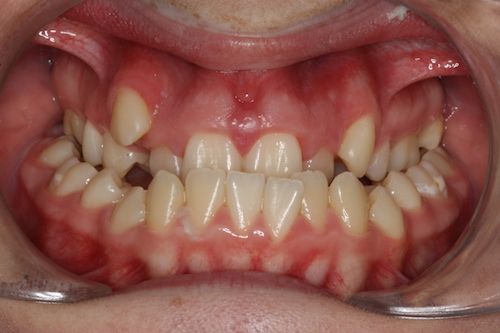

When the bones of the face and jaws are out of balance with each other, orthodontics alone will often not be able to position the teeth in order to create a functional bite. This imbalance between the jaws can result in a combination of problems. These may include:

- Crowded, irregular teeth

Surgery may involve either the upper jaw, lower jaw or both depending on the skeletal discrepancy of your particular case. This will allow the teeth to meet correctly and provide you with an improved bite, and often there is an accompanying improvement in your facial appearance and profile.

Your teeth need to be aligned, levelled and moved into the correct position ready for your jaw surgery to take place and remain stable after the surgery. This can often result in your bite becoming worse over the period of orthodontic treatment, but you have to remember that your teeth will be in a better, more stable position after the jaws have been moved into their correct planned position.

- Improved facial appearance

- Improved function – better bite, no pain / trauma on biting

- Straight teeth